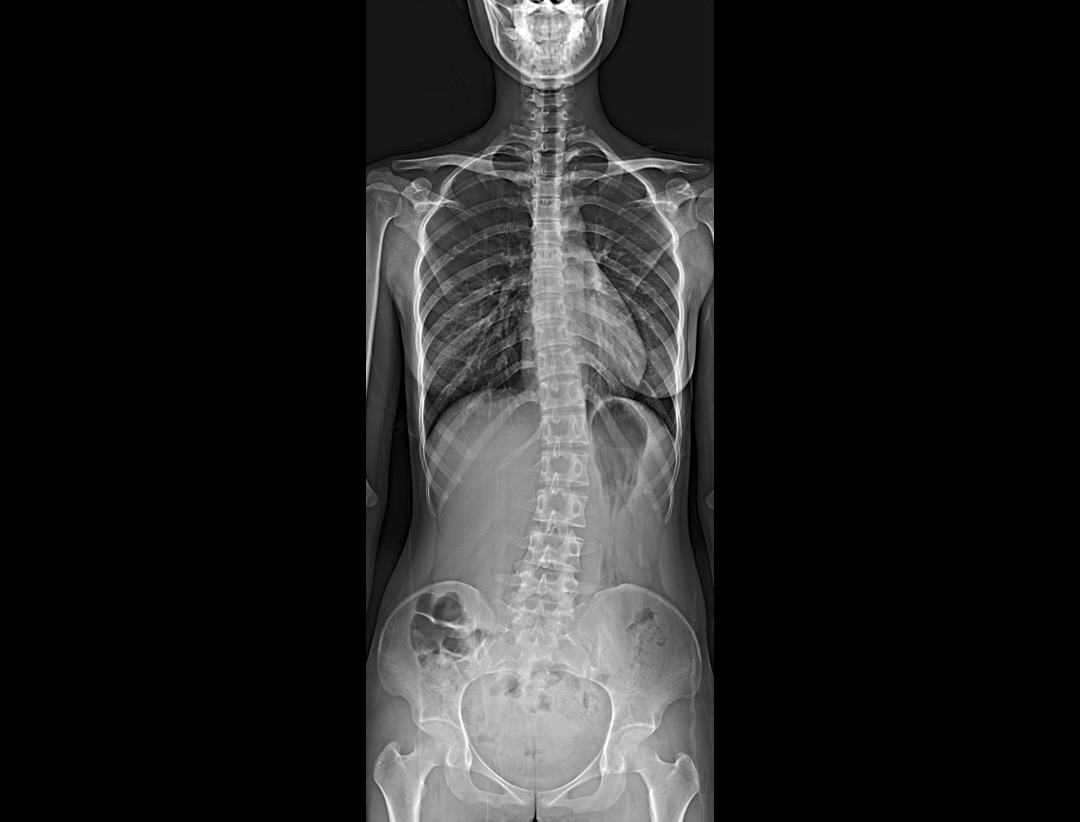

测量功能*

集成脊柱Cobb角及股骨颈干角测量功能,精准指导外科手术及术后评估。